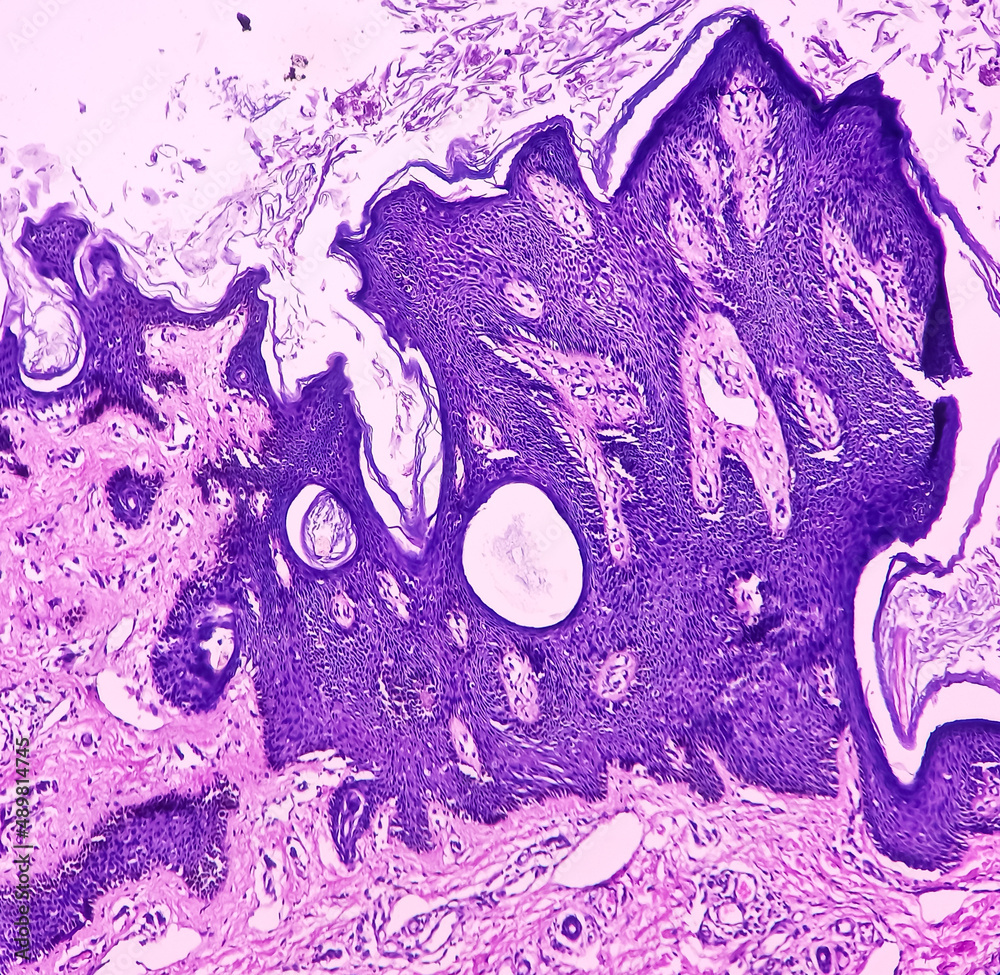

From stock.adobe.com

Stockfoto med beskrivningen Skin(biopsy) Seborrhoeic keratosis, epidermis show hyperkeratosis Horn Cyst Definition The horn is a hard outgrowth of abnormally shaped tissue. It may be pseudo or true. They can be benign, precancerous, or cancerous. A skin horn (also known as a cutaneous horn or cornu cutaneum) is a lesion that resembles an animal horn. Horn cysts represent foci of abrupt complete keratinization (with only a very thin surrounding granular cell layer. Horn Cyst Definition.